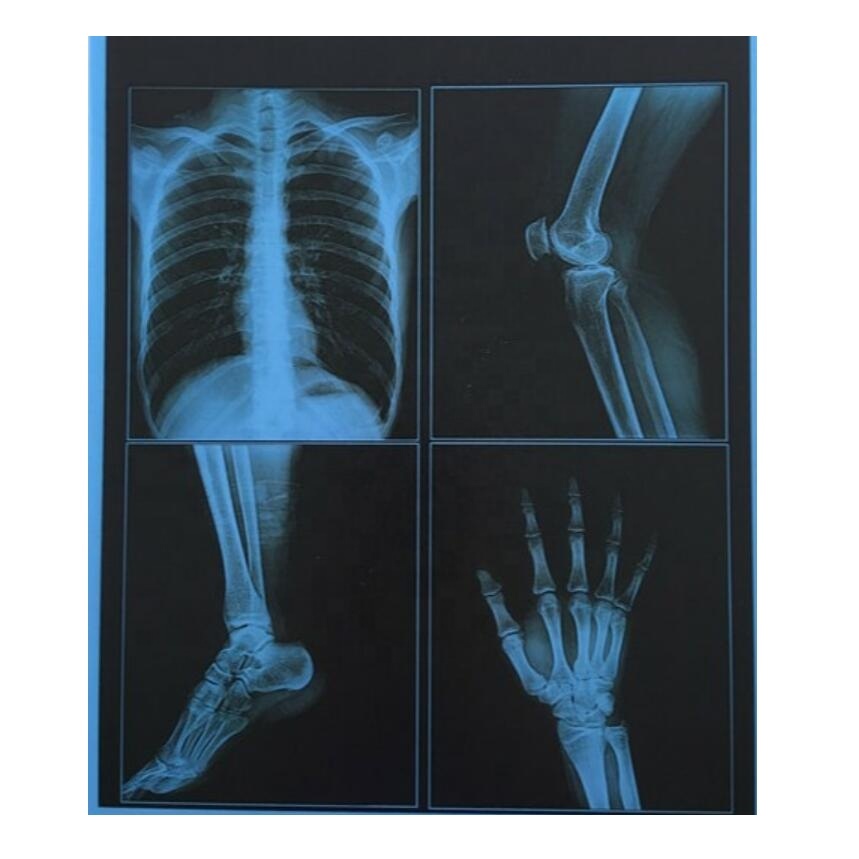

Организация рабочего пространства: стенды для рентгеновских снимков